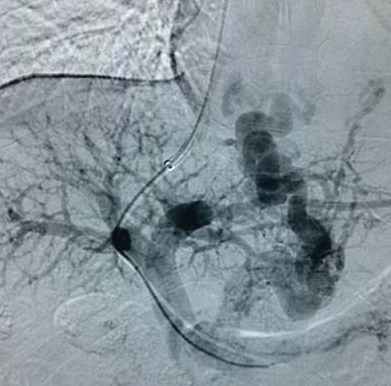

高飞教授与我科王立非主任联合完成了这例手术。TIPS之所以是“高大上”的介入手术,是因为医生手术时虽然只面对一个平面的屏幕,但要在肝内的肝静脉穿刺门静脉,必须要有全面的空间立体感,还要选好支架通道的路径。随着置入肝内支架的打开,门静脉血流瞬间被分流至腔静脉,一条“生命通道”搭建完成,患者门脉压力由术前38mmHg降至术后26mmHg。术后仅是在患者右侧颈部留下5mm大小穿刺口1个,术后患者无再出现呕血,术后7天复查CT显示术前明显迂曲增粗的食管胃底静脉已消失;现患者已康复出院。